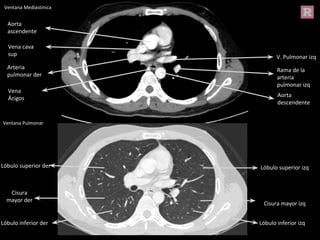

Aorta

descendente

V. Pulmonar izq

Arteria

pulmonar der

Rama de la

pulmonar izq

ascendente

Vena cava

sup

Vena

Ácigos

Cisura

mayor der

Lóbulo superior der

Lóbulo inferior der

Lóbulo superior izq

Lóbulo inferior izq

Cisura mayor izq